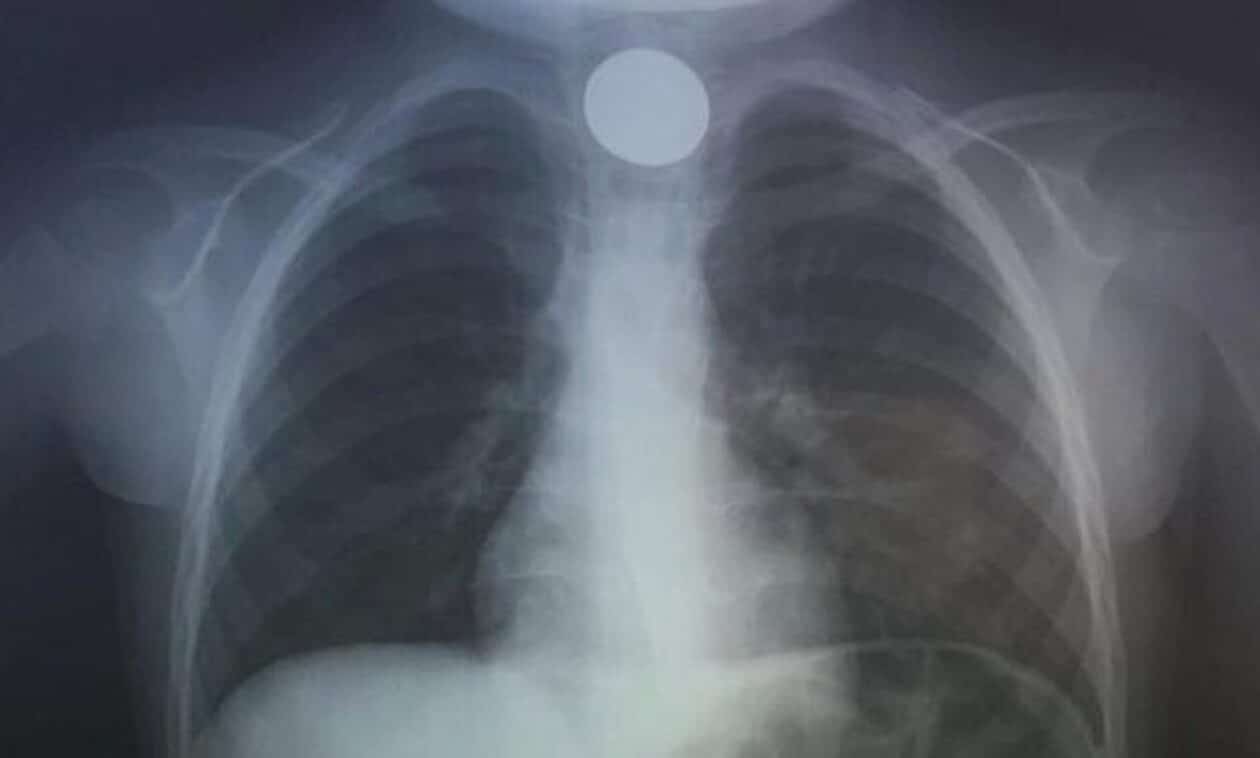

Ηράκλειο: Οι γιατροί προχώρησαν σε επείγουσα αφαίρεση του ξένου σώματος

Εσπευσμένα στο νοσοκομείο μεταφέρθηκε παραμονή Πρωτοχρονιάς ένα παιδί μόλις 4 χρονών.

Όπως αναφέρει το cretapost, το 4χρονο παιδί είχε καταπιεί ένα κέρμα και δεν μπορούσε να αναπνεύσει.

Άμεσα οδηγήθηκε στο ΠΑΓΝΗ με τους γιατρούς να προχωρούν σε επείγουσα αφαίρεση η οποία στέφθηκε με επιτυχία.

Το περιστατικό γνωστοποιήθηκε από την ΩΡΛ κλινική του νοσοκομείου μέσω ανάρτησης στα social media: